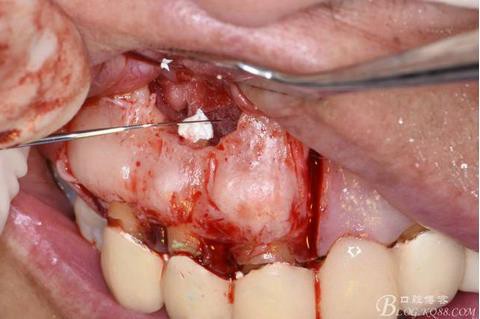

圖13.根尖倒預備

圖14.吸潮紙尖干燥根管